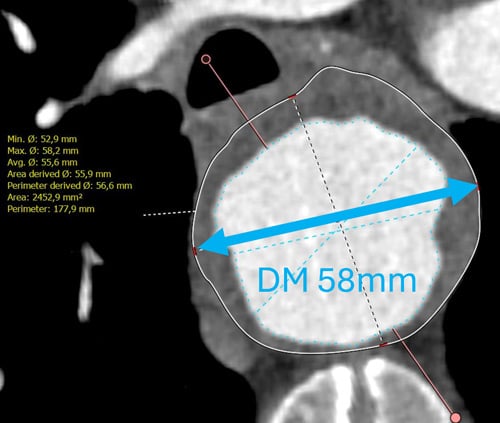

This challenging case features a 65-year-old patient with multiple comorbidities, a 58 mm thoracic aneurysm, and a severely kinked, diseased aorta.

- Progressive aneurysm, diameter 58 mm.

- Kinked anatomy (proximal descending!).